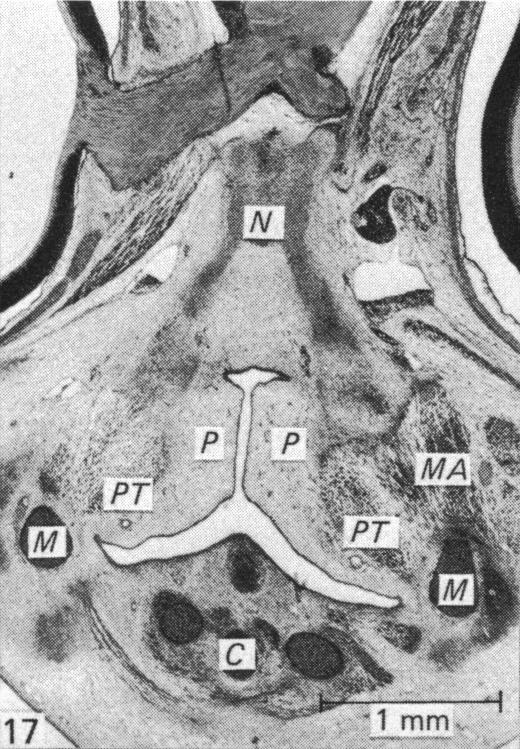

The mesencephalic neural crest cells of Hamburger-Hamilton Stage 9-Stage 11 chick embryos were surgically extirpated unilaterally in 148 embryos and bilaterally in 8 embryos. Sham operations were performed unilaterally on 16 control embryos and bilaterally on one control embryo. Embryos were fixed at various time intervals after operation, studied macroscopically, and by light and scanning electron microscopy, and their development compared with that of 47 normal embryos. The extirpated mesencephalic region was repopulated by crest cells within 6-8 hours after operation. These 'new' crest cells migrated from adjacent neuraxial levels (principally the metencephalon and prosencephalon) along the basement membrane of the neural tube and the regenerating ectoderm. At prosencephalic and metencephalic levels, both intrinsic hyperplasia of migrating cells and prolonged migration of crest cells from the dorsomedian part of the neural tube contributed the additional cells required to repopulate the mesencephalic region. Morphogenesis and differentiation of all crest cell derivatives were normal and craniofacial malformations were absent. Thus the neural crest and neural tube can compensate for an extensive regional loss, premigratory crest cells are neither regionally patterned nor determined (as prosencephalic and metencephalic cells give rise to normal mesencephalic derivatives) and regional failure of crest cell formation is an unlikely facial pathogenetic mechanism. Previous workers who observed facial malformations following crest cell extirpations performed the latter by removing the lips of the neural tube which not only removed the crest cells but also the compensatory mechanism. Cervical scoliosis was observed in extirpated embryos but not in controls. The pathogenesis of this scoliosis may be related to the process of compensation, which could disturb the sequential differentiation of the neural tube and so disorganise the mechanisms of normal axial flexion. These observations may be relevant to the pathogenesis of some forms of congenital and infantile idiopathic scoliosis; such scoliosis in man is frequently present in neurofibromatosis--a neural crest lesion.